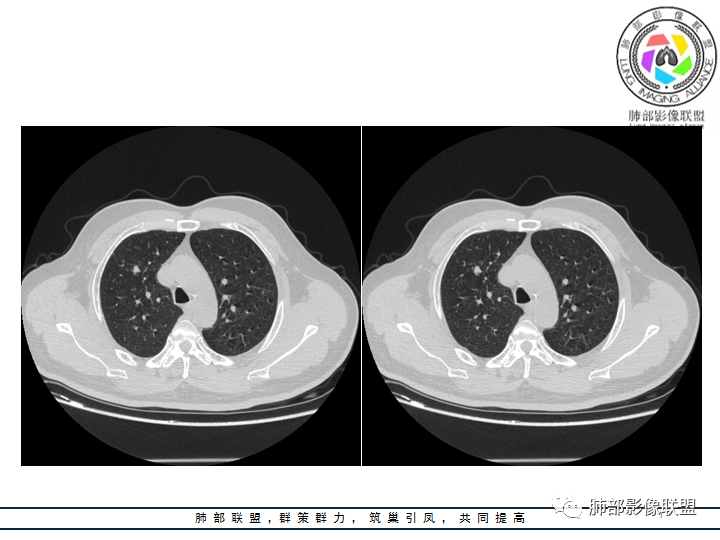

影像资料

老年男性患者,长期吸烟史,没有呼吸系统临床表现。胸部CT示右肺上叶实性密度结节影,密度均匀,未见空洞及钙化,边缘较光整,未见分叶及毛刺。血管影旁现侧出,支气管进入并截断,不均匀强化。